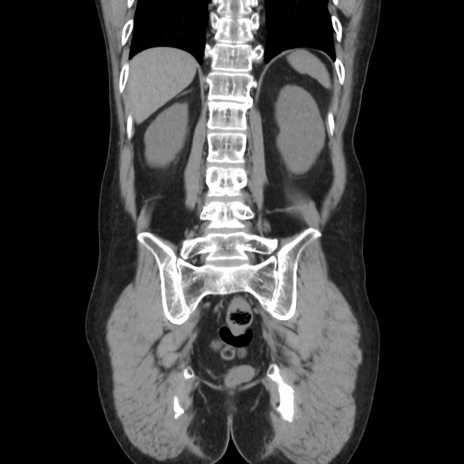

症例37(冠状断像)

【症例】40歳代 男性

【主訴】腹痛

【現病歴】4時間ほど前に電車に乗車中に臍部上より腹痛出現。徐々に増悪し起立困難となり、救急外来受診。生ものは数日食べていない。今朝お雑煮を食べた。

【身体所見】BT 36.8℃、BP 117/84mmHg、HR 91/min、SpO2 97%、苦悶様、腹部:臍上部広範囲圧痛あり、反跳痛±

【データ】WBC 8100、CRP 0.03